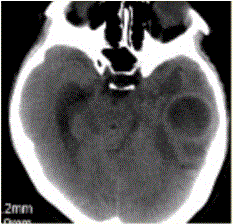

问题 患者女,26岁,头痛、低热10d余,既往有左侧慢性中耳炎病史。CT表现如下图。 有关脑脓肿的DWI表现,正确的是

选项 A.DWI上脓肿腔均呈高信号,ADC呈低信号 B.经过治疗的脓肿腔DWI也可呈等信号或低信号 C.DWI脓肿周围水肿高信号,ADC高信号 D.DWI上脓肿腔低信号,ADC高信号 E.脓肿壁DWI高信号